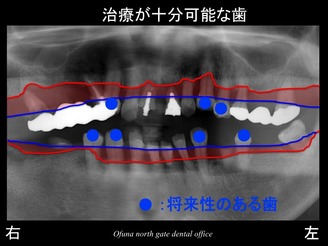

いつものように 骨吸収の状態を分かりやすくするために

骨吸収の状態を線で書いたのが以下のレントゲンになります。

青線が骨吸収を起こす前の骨の位置です。

赤線は、現在の骨の位置です。

さらに分かりやすくするために 骨吸収部位を赤色の領域で表しします。

骨吸収が非常に大きいのが分かります。

逆に治療が可能な歯は以下の歯です。

歯周病治療、虫歯の治療…等を行うことにより治療が可能な歯です。